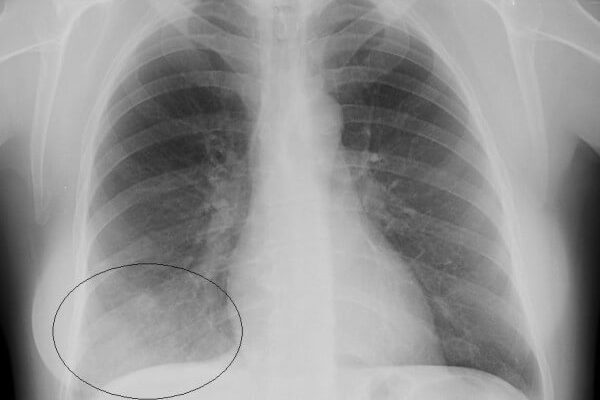

- На рентгенограмме виден участок поражения — местное потемнение при пневмонии.

Правильный диагноз может поставить только специалист после рентгенографии легких — затемнения могут наблюдаться при пневмонии. Ухудшить положение пациента могут различные факторы: